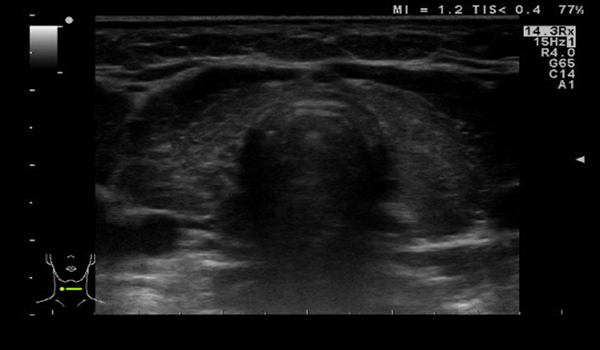

Hashimoto thyroiditis

Thyroid ultrasound (transverse view): marked reduction in size and a heterogenous, flaky echoic structure suggesting inflammatory infiltration.

The thyroid is significantly hypoechoic and its appears lumpy compared to the surrounding muscles